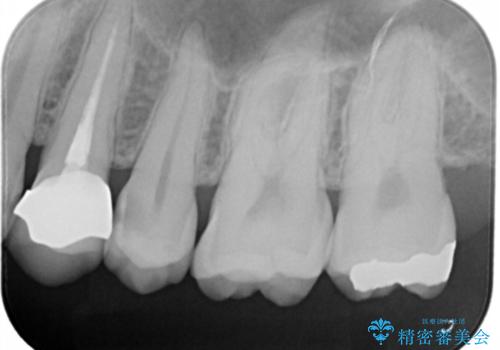

う蝕除去中に露髄 フルジルコニアクラウン

う蝕が神経近接にまで達していたので露髄する可能性を説明しました。

その場合、精密根管治療・クラウンになることもお伝えしています。

う蝕除去中に露髄したため精密根管治療へと切り替え、仮歯をはさんでセラミッククラウンを装着し終了としました。

*根管治療は保険を希望されました。